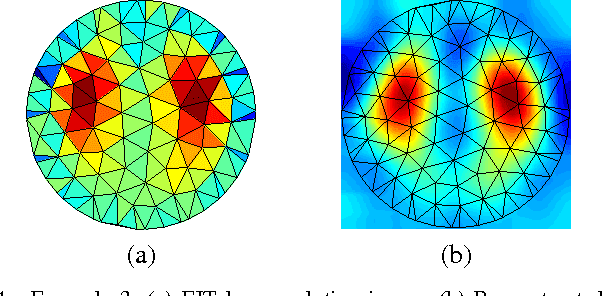

Super-Resolution Reconstruction of Electrical Impedance Tomography Images

May 15, 2018

Abstract:Electrical Impedance Tomography (EIT) systems are becoming popular because they present several advantages over competing systems. However, EIT leads to images with very low resolution. Moreover, the nonuniform sampling characteristic of EIT precludes the straightforward application of traditional image ruper-resolution techniques. In this work, we propose a resampling based Super-Resolution method for EIT image quality improvement. Preliminary results show that the proposed technique can lead to substantial improvements in EIT image resolution, making it more competitive with other technologies.